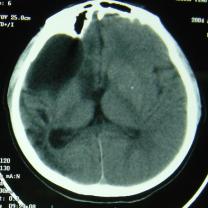

CT檢查:右額部見邊緣清晰的腦脊液密度區(qū),大小約82mm×52mm,與側(cè)腦室相溝通,內(nèi)側(cè)達(dá)中線,其內(nèi)可見帶狀分隔;右側(cè)顳頂葉及部分枕葉腦組織呈低密度改變,左側(cè)側(cè)腦室形態(tài)、大小正常,中線結(jié)構(gòu)尚居中(圖1)。

圖1 CT(①②)顯示右額部邊緣清晰的腦脊液密度區(qū)與側(cè)腦室相溝通,其內(nèi)可見帶狀分隔;右側(cè)顳頂葉及部分枕葉腦組織呈低密度改變